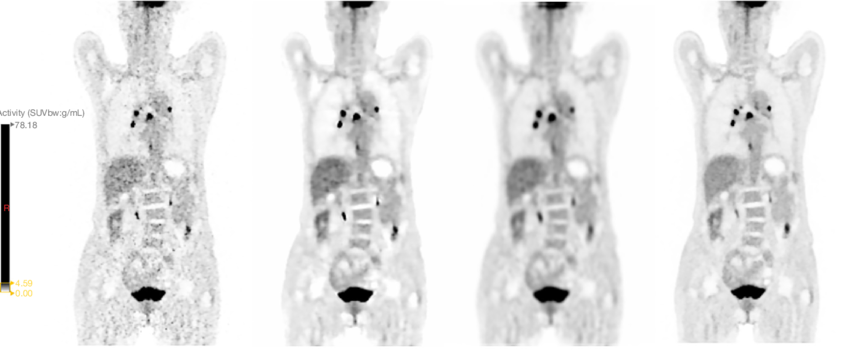

Ricostruzione e miglioramento dell’immagine: grazie al deep learning (es. modelli 3D U-Net), è possibile ottenere immagini diagnostiche di alta qualità partendo da dati acquisiti con dosi di tracciante ridotte fino a un centesimo. Il processo di addestramento consiste nel fornire al modello un’immagine a bassa dose (“brutta”) e l’immagine finale ad alta risoluzione, lasciando che l’algoritmo impari autonomamente la trasformazione. Questo, sebbene rivoluzionario, solleva il problema della “scatola nera”, in quanto il processo decisionale interno del modello non è trasparente.

Contouring automatizzato del volume tumorale: il contouring manuale, descritto come “indaginoso, laborioso, time consuming, operatore dipendente”, viene trasformato dall’AI. I tempi si riducono drasticamente, passando da 2 ore a 20 minuti, fino a 2 minuti per paziente. Questo non solo genera un enorme guadagno di efficienza, ma introduce un livello di oggettività senza precedenti, permettendo di identificare, misurare e confrontare le lesioni nel tempo per una valutazione più accurata della risposta alla terapia.

L’utilità del contouring basato su AI (come le reti U-Net) risiede in un paradosso apparente: il suo successo si misura proprio dalla sua indistinguibilità dal lavoro manuale.

Quando addestriamo questi algoritmi, utilizziamo come ‘Gold Standard’ i contorni tracciati da medici esperti. L’AI impara a replicare quelle stesse curve, includendo correttamente il GTV (volume tumorale) e risparmiando gli organi a rischio (OAR), esattamente come farebbe un operatore umano.

Dal punto di vista qualitativo, quindi, non cambia molto: il risultato finale è clinicamente sovrapponibile. La rivoluzione è nel flusso di lavoro. Il contouring manuale è un compito ripetitivo, ‘time-consuming’ e soggetto a stanchezza. L’AI trasforma il ruolo del medico nucleare o del radioterapista: non più ‘disegnatore’ che parte da un foglio bianco, ma ‘supervisore’ che valida un lavoro già fatto.

L’AI fornisce una bozza ad alta fedeltà. Se la differenza geometrica è minima, il guadagno in termini di tempo e la standardizzazione del metodo (riducendo la variabilità inter-operatore) rappresentano il vero valore aggiunto per il sistema sanitario.